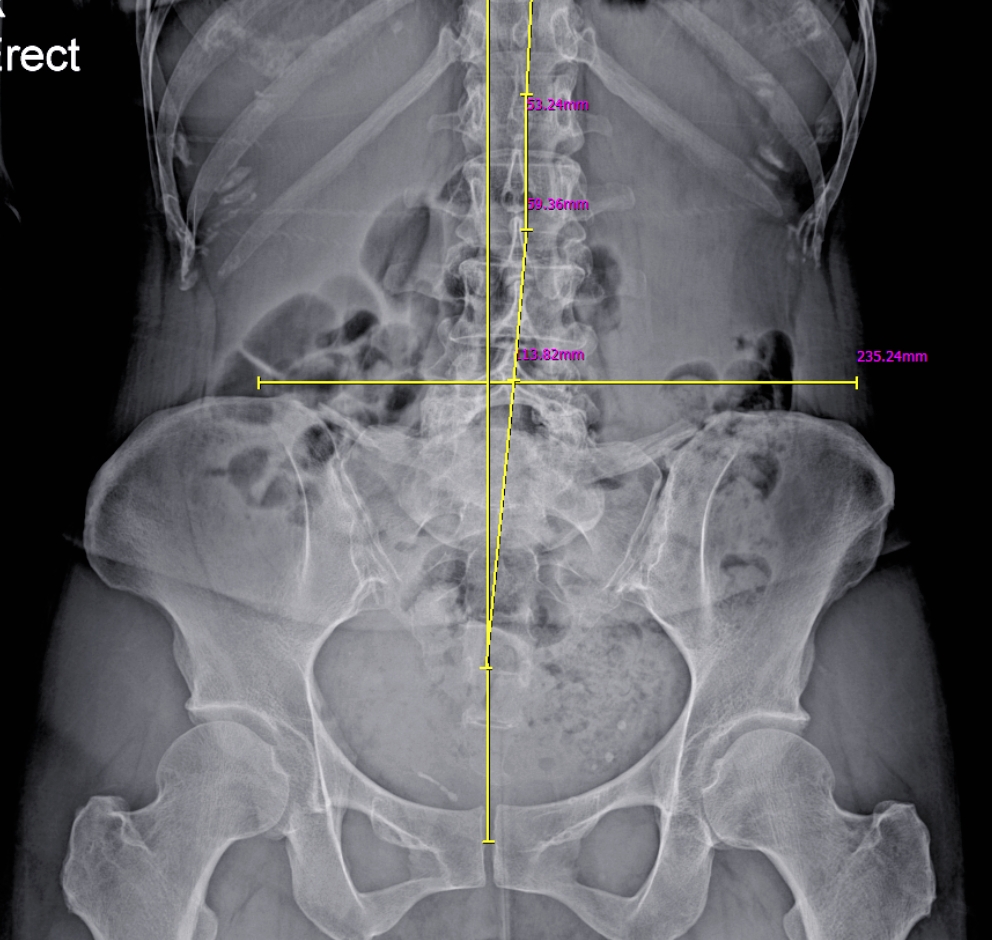

여러분의 발은 가만히 있는 상태와 움직이는 상태에서 매우 다른 모습을 보입니다. 맞춤 깔창을 선택할 때 단순히 발의 정적인 모양만 측정하는 것은 큰 위험을 초래할 수 있습니다. 걸을 때는 복잡한 생체역학적인 움직임이 이루어지기 때문입니다. 단순히 서 있는 상태의 발 모양만으로 깔창을 제작하면, 실제 보행 중에 발이 안쪽 혹은 바깥쪽으로 과도하게 회전할 가능성이 큽니다. 이를 과회내(Overpronation)이나 과회외(Supination)라고 하며, 이로 인해 발목, 무릎, 고관절 등 다양한 부위의 통증이 만성화될 수 있습니다. 저희 시지다나아마취통증의학과의원에서는 이와 같은 문제를 방지하기 위해 철저한 보행 분석(Gait Analysis)를 통해 발의 동적 움직임을 면밀히 평가합니다. 이를 통해 환자 여러분에게 맞춤화된 깔창을 제공하여 최상의 컨디션을 유지할 수 있도록 도와드리고 있습니다.